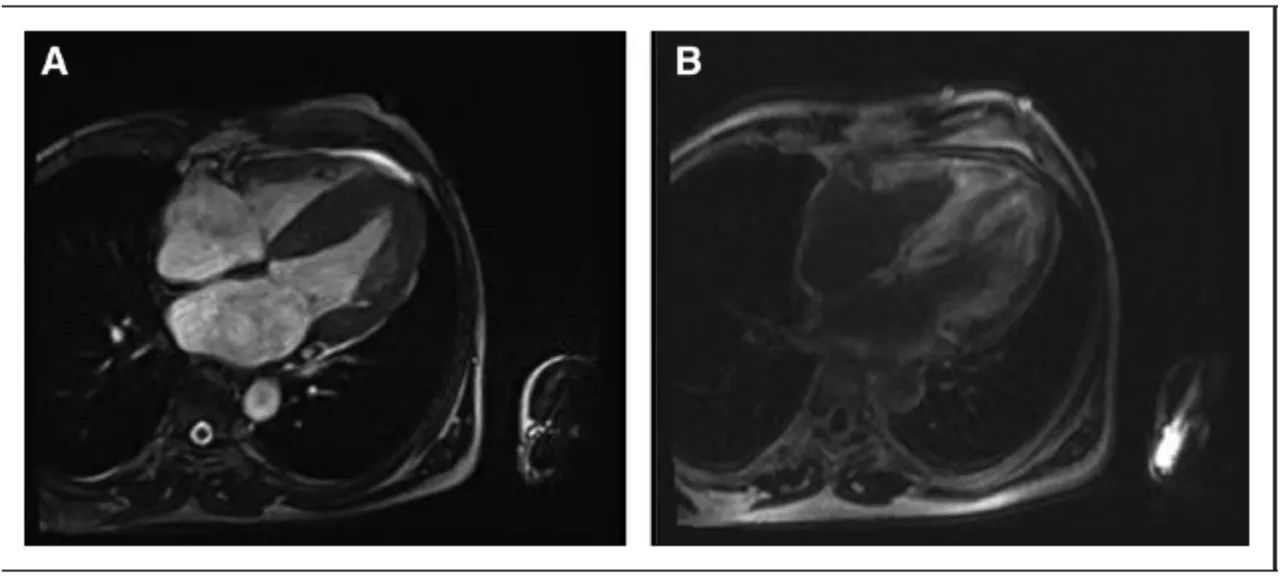

心肌淀粉样变MRI:A 心肌肥厚;B 全层心肌钆延迟显像(LGE)

(Circ Res. 2017;121:819-837)

CMR(CA)

T1 值提示细胞外弥漫淀粉样蛋白和水肿•

T1 mapping 定量心肌细胞外间质淀粉样蛋白的容积,容积增加提示细胞外水肿,淀粉样物质进展,提示LA患者死亡率增加。

(CircRes.2017;121:819-837.)